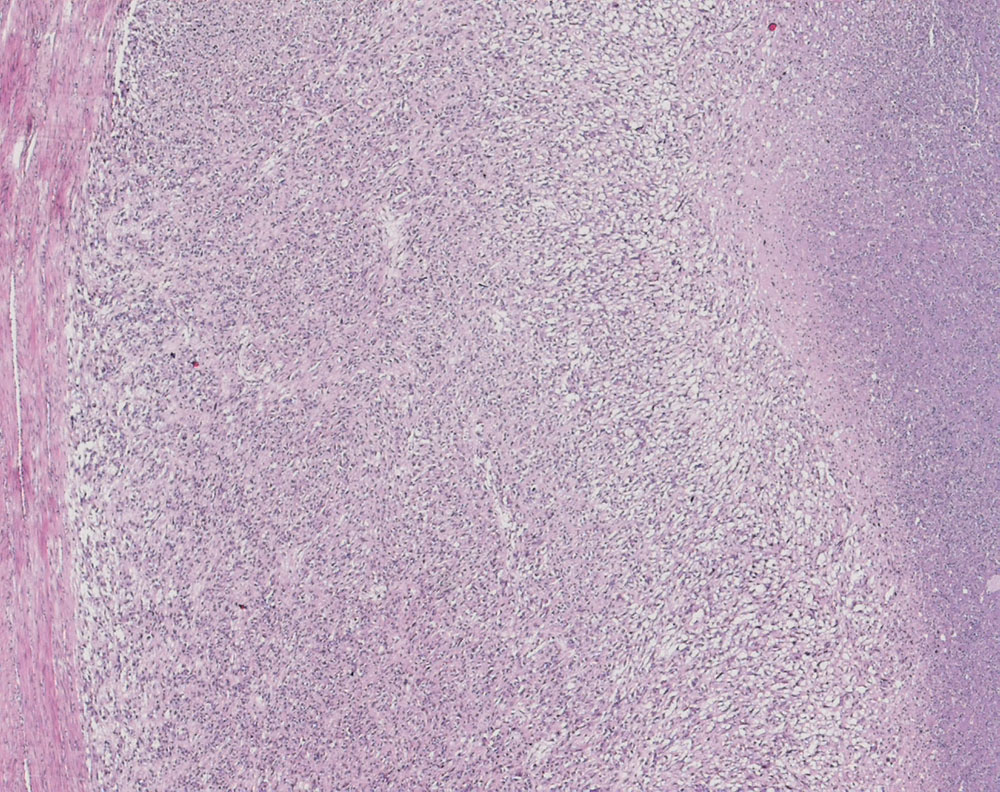

PathoPic ID 10239 - Uterines Leiomyosarkom

Uterines Leiomyosarkom

maligner Tumor

Uterus

Genitalorgane, weiblich

Links im Bild ein schmaler Saum

Myometrium. Das

Sarkom ist relativ scharf davon abgegrenzt und deutlich Zellreicher. Rechts im Bild

Tumornekrose.

Durchmesser 16cm. 28 Mitosen/10 HPF. Tumornekrosen >50%. Gefässinvasion.

Uterus myomatosus

Histologie

25